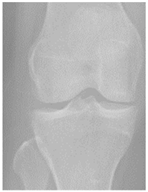

In the local dataset, we have selected 60 adult patient files of men and women with knee disorders who were radiographically examined at the Radiology Department of the El Kelaa des Sraghna Provincial Hospital. Each file consists of one or more knee radiographs in Dicom format as presented in Figure 7. The images were acquired using a standard ITALRAY radiology table. After analysis, 30 images with implants and non-posterior-anterior examination views were excluded and 30 left and right Dicom knees were retained to validate this work. To make the validation local dataset, the ROI was selected manually as illustrated in Figure 8. Then, each patient’s file was presented to a rheumatologist with PNG images. In case of disagreement between our diagnostic system and the rheumatologist, a radiologist was consulted for arbitration to make the final decision.

Figure 7.

Example of knee X-ray images collected and filtered from patients with knee symptoms.